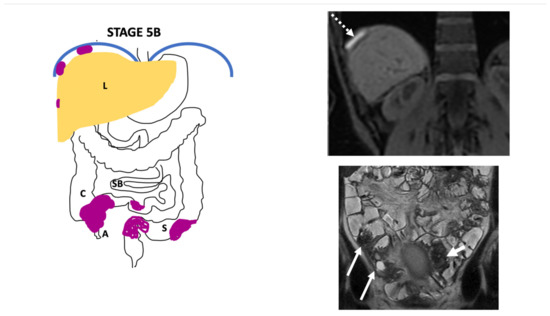

3. The Endo-Stage Mri Classification

| Endo-Stage MRI | Location | Extent | Risk Stratification |

|---|---|---|---|

| Endo-Stage MRI 0 | Superficial endometriosis |

| Low |

| Endometriosis is strictly confined to the ovaries |

| ||

| Endo-Stage MRI I | Endometriosis is strictly confined to the retrocervical area |

| |

| Endo-Stage MRI II | Endometriosis invades beyond the retrocervical area, but not to the pelvic side-wall |

| Endo-Stage MRI III | Endometriosis extends to the pelvic side-wall and/or causes hydronephrosis or non-functioning kidney |

| Intermediate |

| Endo-Stage MRI IV | Endometriosis has involved the bladder or rectosigmoid colon |

| Endo-Stage MRI V | Multiple deep endometrioticlocations |

| High |